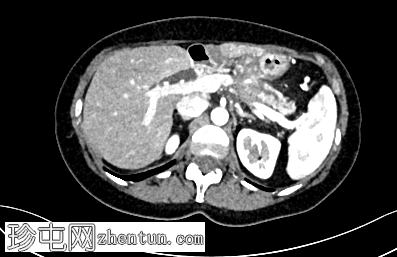

冠状位增强扫描

动脉期

术后改变符合慢性胰腺炎Beger手术的影像学表现。胰头显影良好,结构完整;胰尾可见主胰管扩张,系远端胰肠吻合口处浸润性肿块所致。该肿块浸润脾动脉和脾静脉,并伴有血管周围侵犯,以及胰周脂肪浸润。此外,肠系膜可见线状软组织密度影,提示腹膜播散。

左肝叶偶见海狸尾状解剖变异。